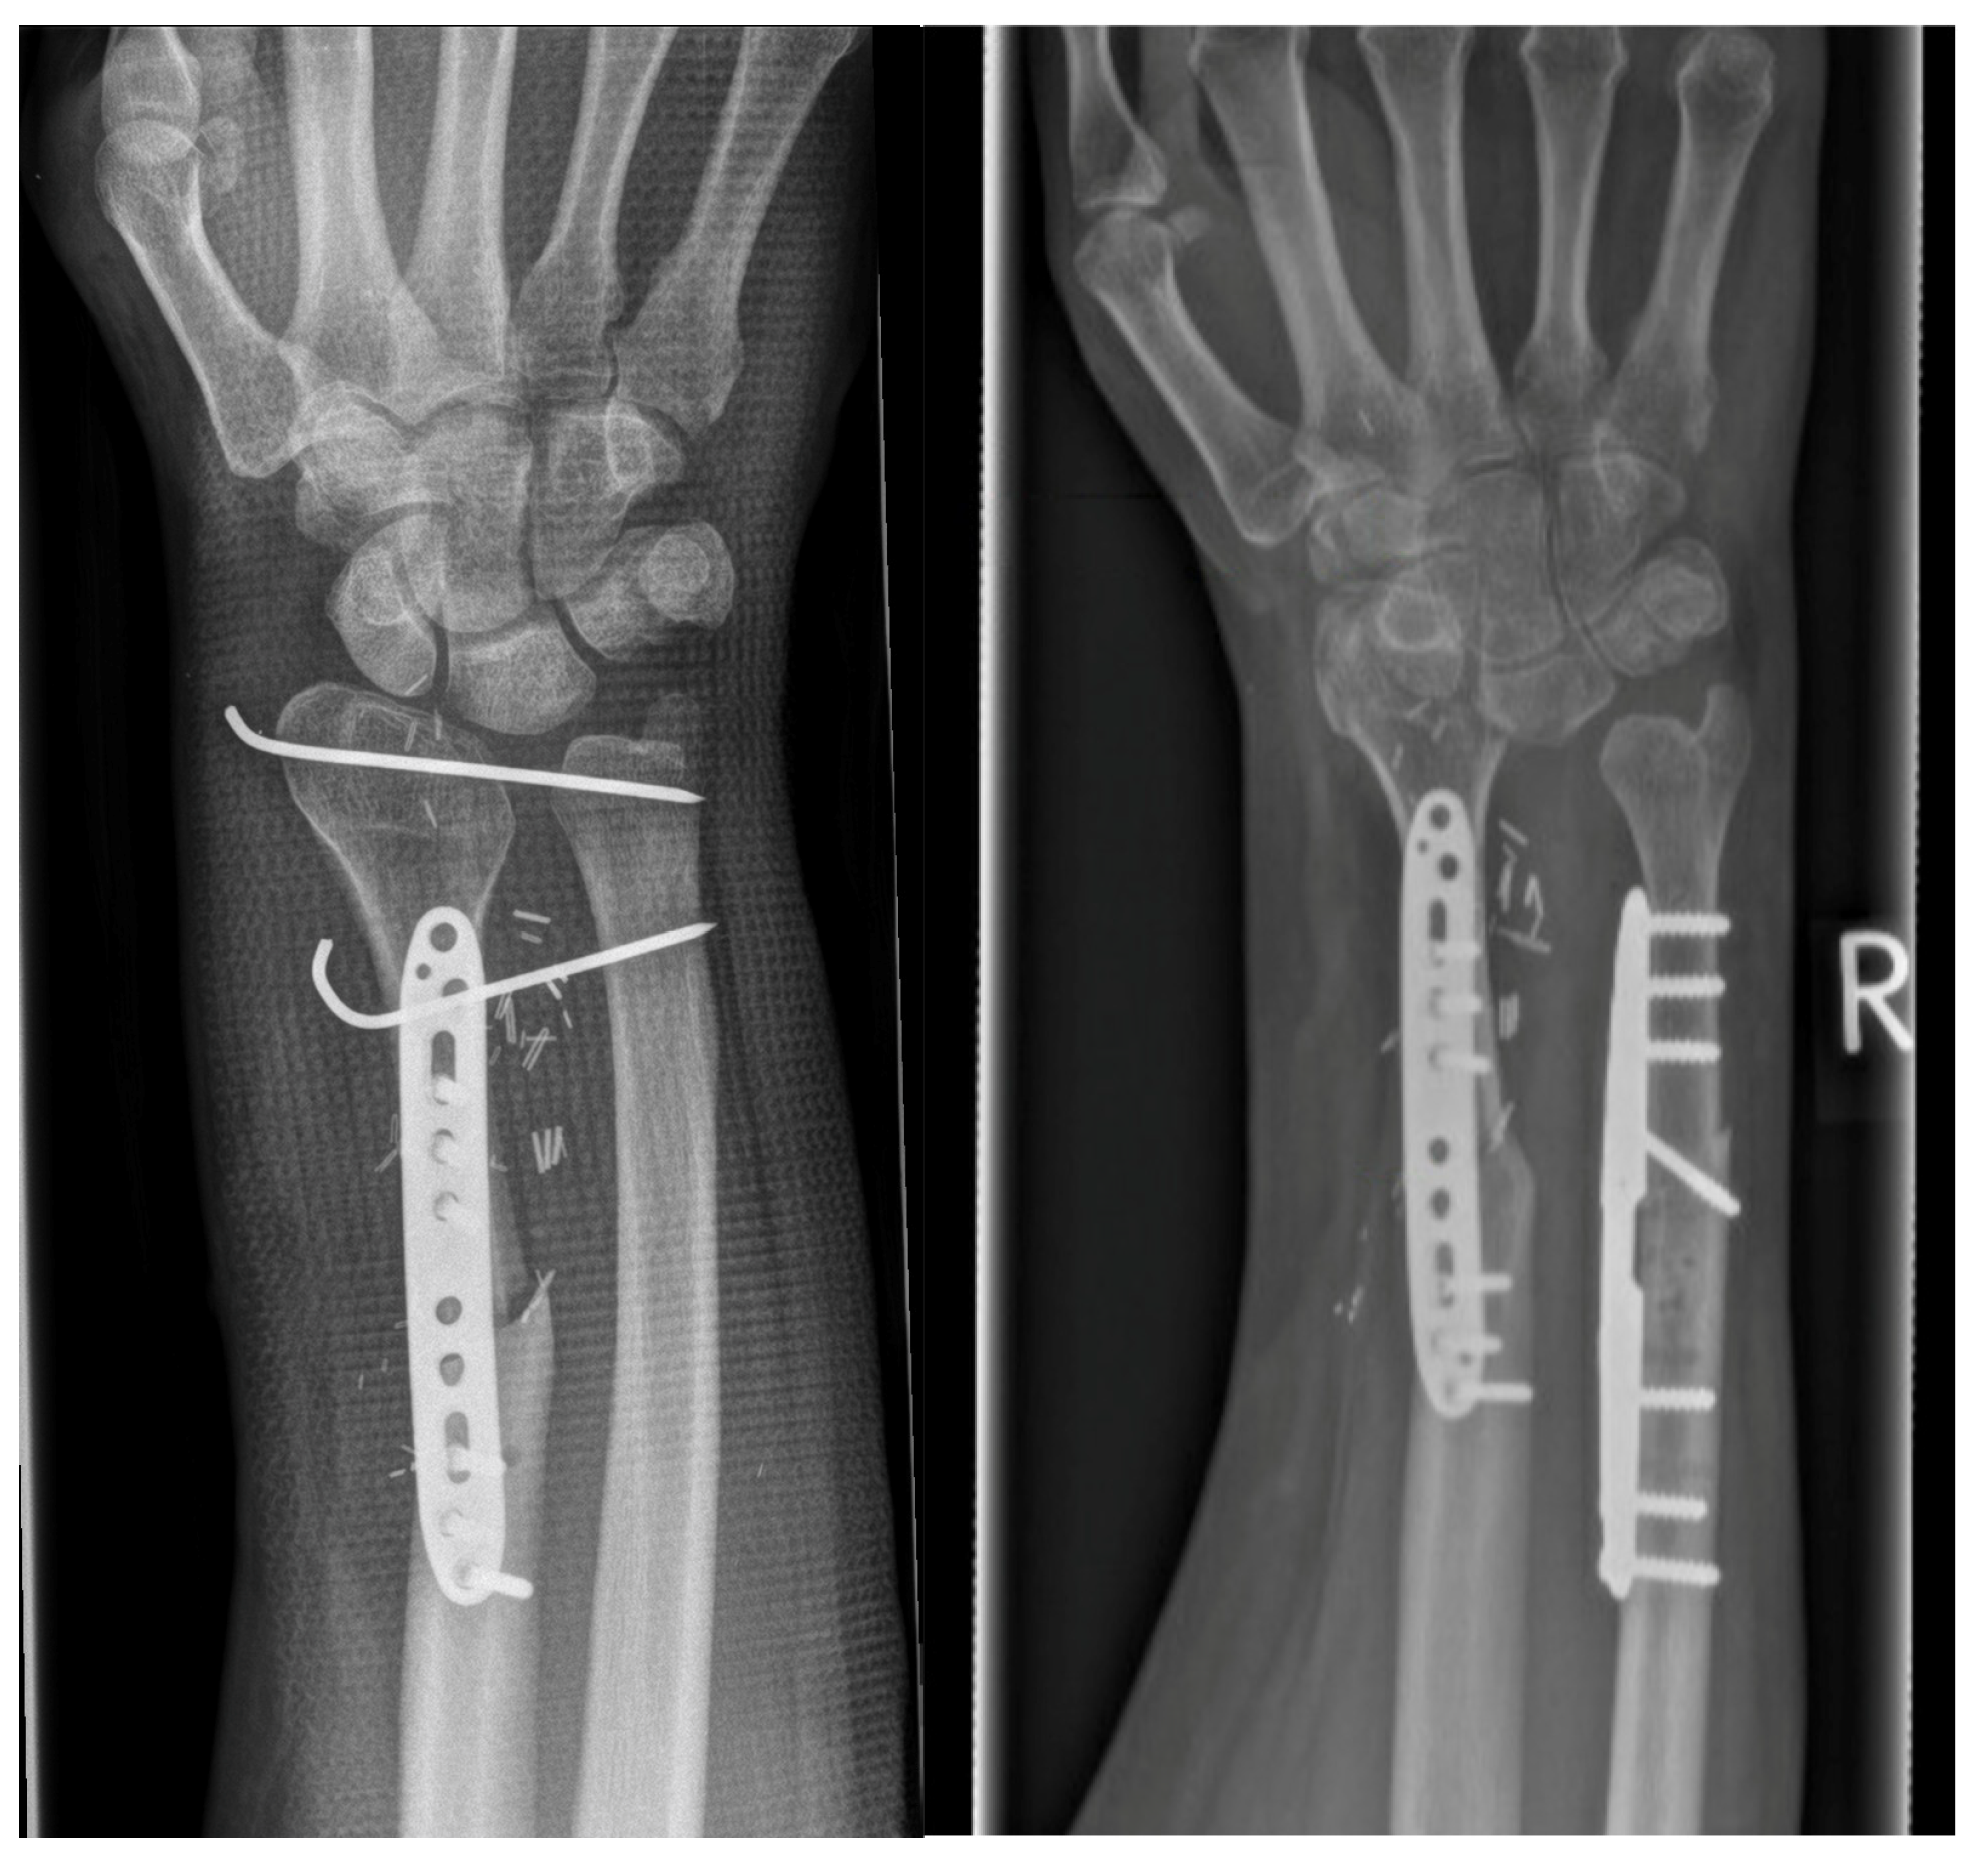

Arthrodesis of the Wrist with Vascularized Fibula Flap for the Treatment of a Large Defect of the Distal Radius

| GROUP 1 | Case 1 | Distal radius, parts of the proximal wrist | Trauma | 6 month | 32 | 9 cm | Vascularized fibula | Wrist arthrodesis | N/A N/A | 0-0-0° 40-0-50° | 60% | MMWS = 50 DASH = 24 | yes |